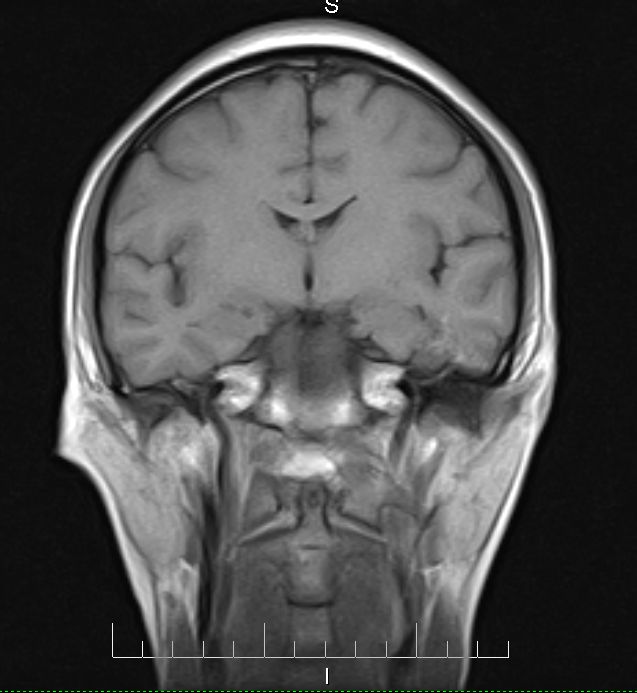

标题: MRI2379:30岁,男,癫痫10年,请各位看一下;CT示:左颞叶钙 [打印本页]

标题: MRI2379:30岁,男,癫痫10年,请各位看一下;CT示:左颞叶钙

左颞叶区见不规则点状混杂信号影

支持2楼 左颞叶区见不规则点状混杂信号影,考虑动静脉畸形。

考虑左侧颞叶脑血管畸形(avm)。----t1低等高混杂信号,t2等高信号周边较多流空血管影[冠状位明显],mra左侧大脑中动脉受压,远侧聚集.